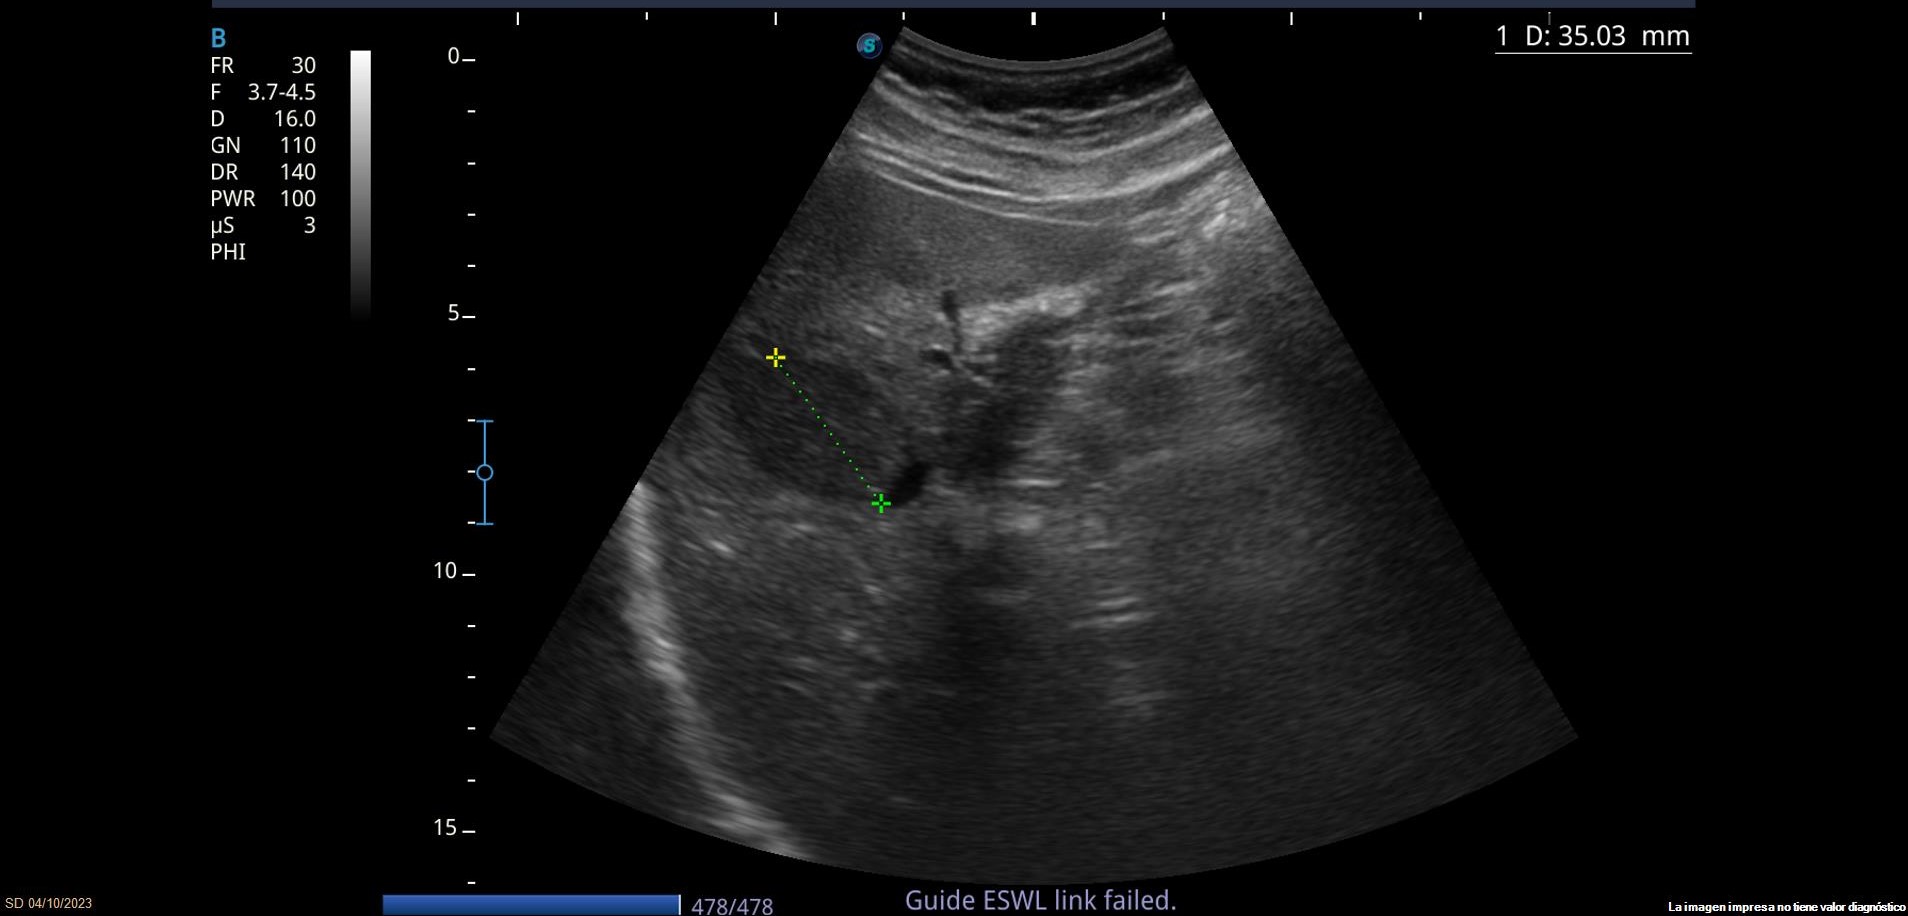

Se observan varias LOEs (lesiones ocupantes de espacio) hepáticas isoecoicas con parénquima hepático, la mayor de 3.5cm de diámetro, con leve vascularización. También se observa lesión hiperecoica con sombra posterior en parénquima hepático, sugerente de litiasis.